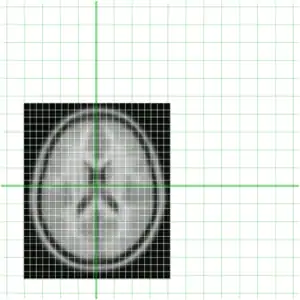

To get an idea of how they currently overlay I have put them together below

Clearly they are not aligned or "registered" to each other so we have to use a tool such as minctracc or mritoself in order to align them as such: